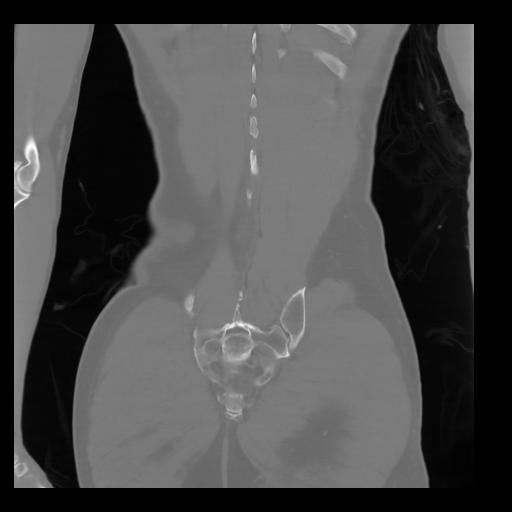

35 CUERPO,CE,Coronal,3.000,CUERPO,Coronal,